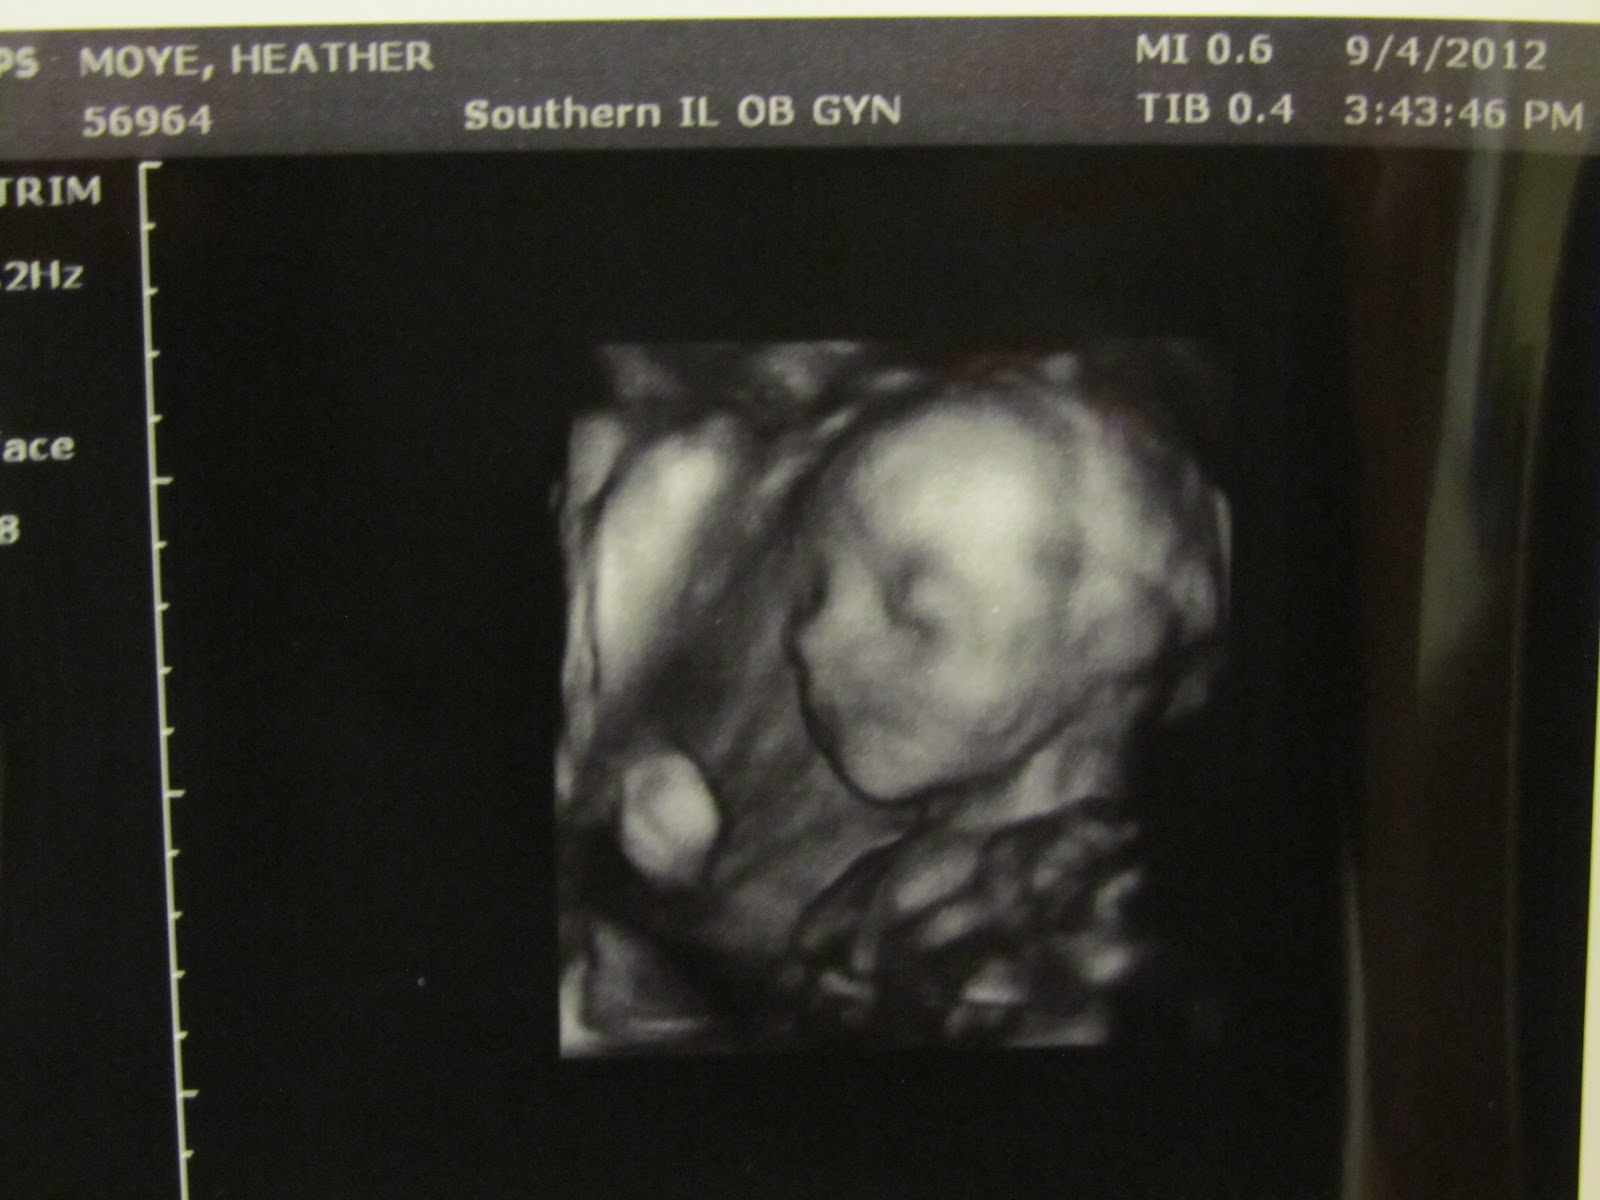

Our appointment was yesterday where we had a second ultrasound to check the weight and size of the baby. Turns out our baby is the perfect size for a Decemeber 28th due date! Looks like we may have an after Christmas baby! Everything so far looks great. I couldn't believe how much he has changed in just a month's time. Through the whole thing he was moving like crazy! By the time I went to bed last night, he was all I could feel. I definitely will not complain though! Our next appointment is October 3rd where I will have my glucose test. Please pray that all will go well! Our plans for the next month are to begin the painting process, look for new flooring, and registering at Target.

I have added some new pictures below for our little Boy Moye! God has truly blessed us!

Here are our new pictures of our little guy!

Just look at his little face!!!!